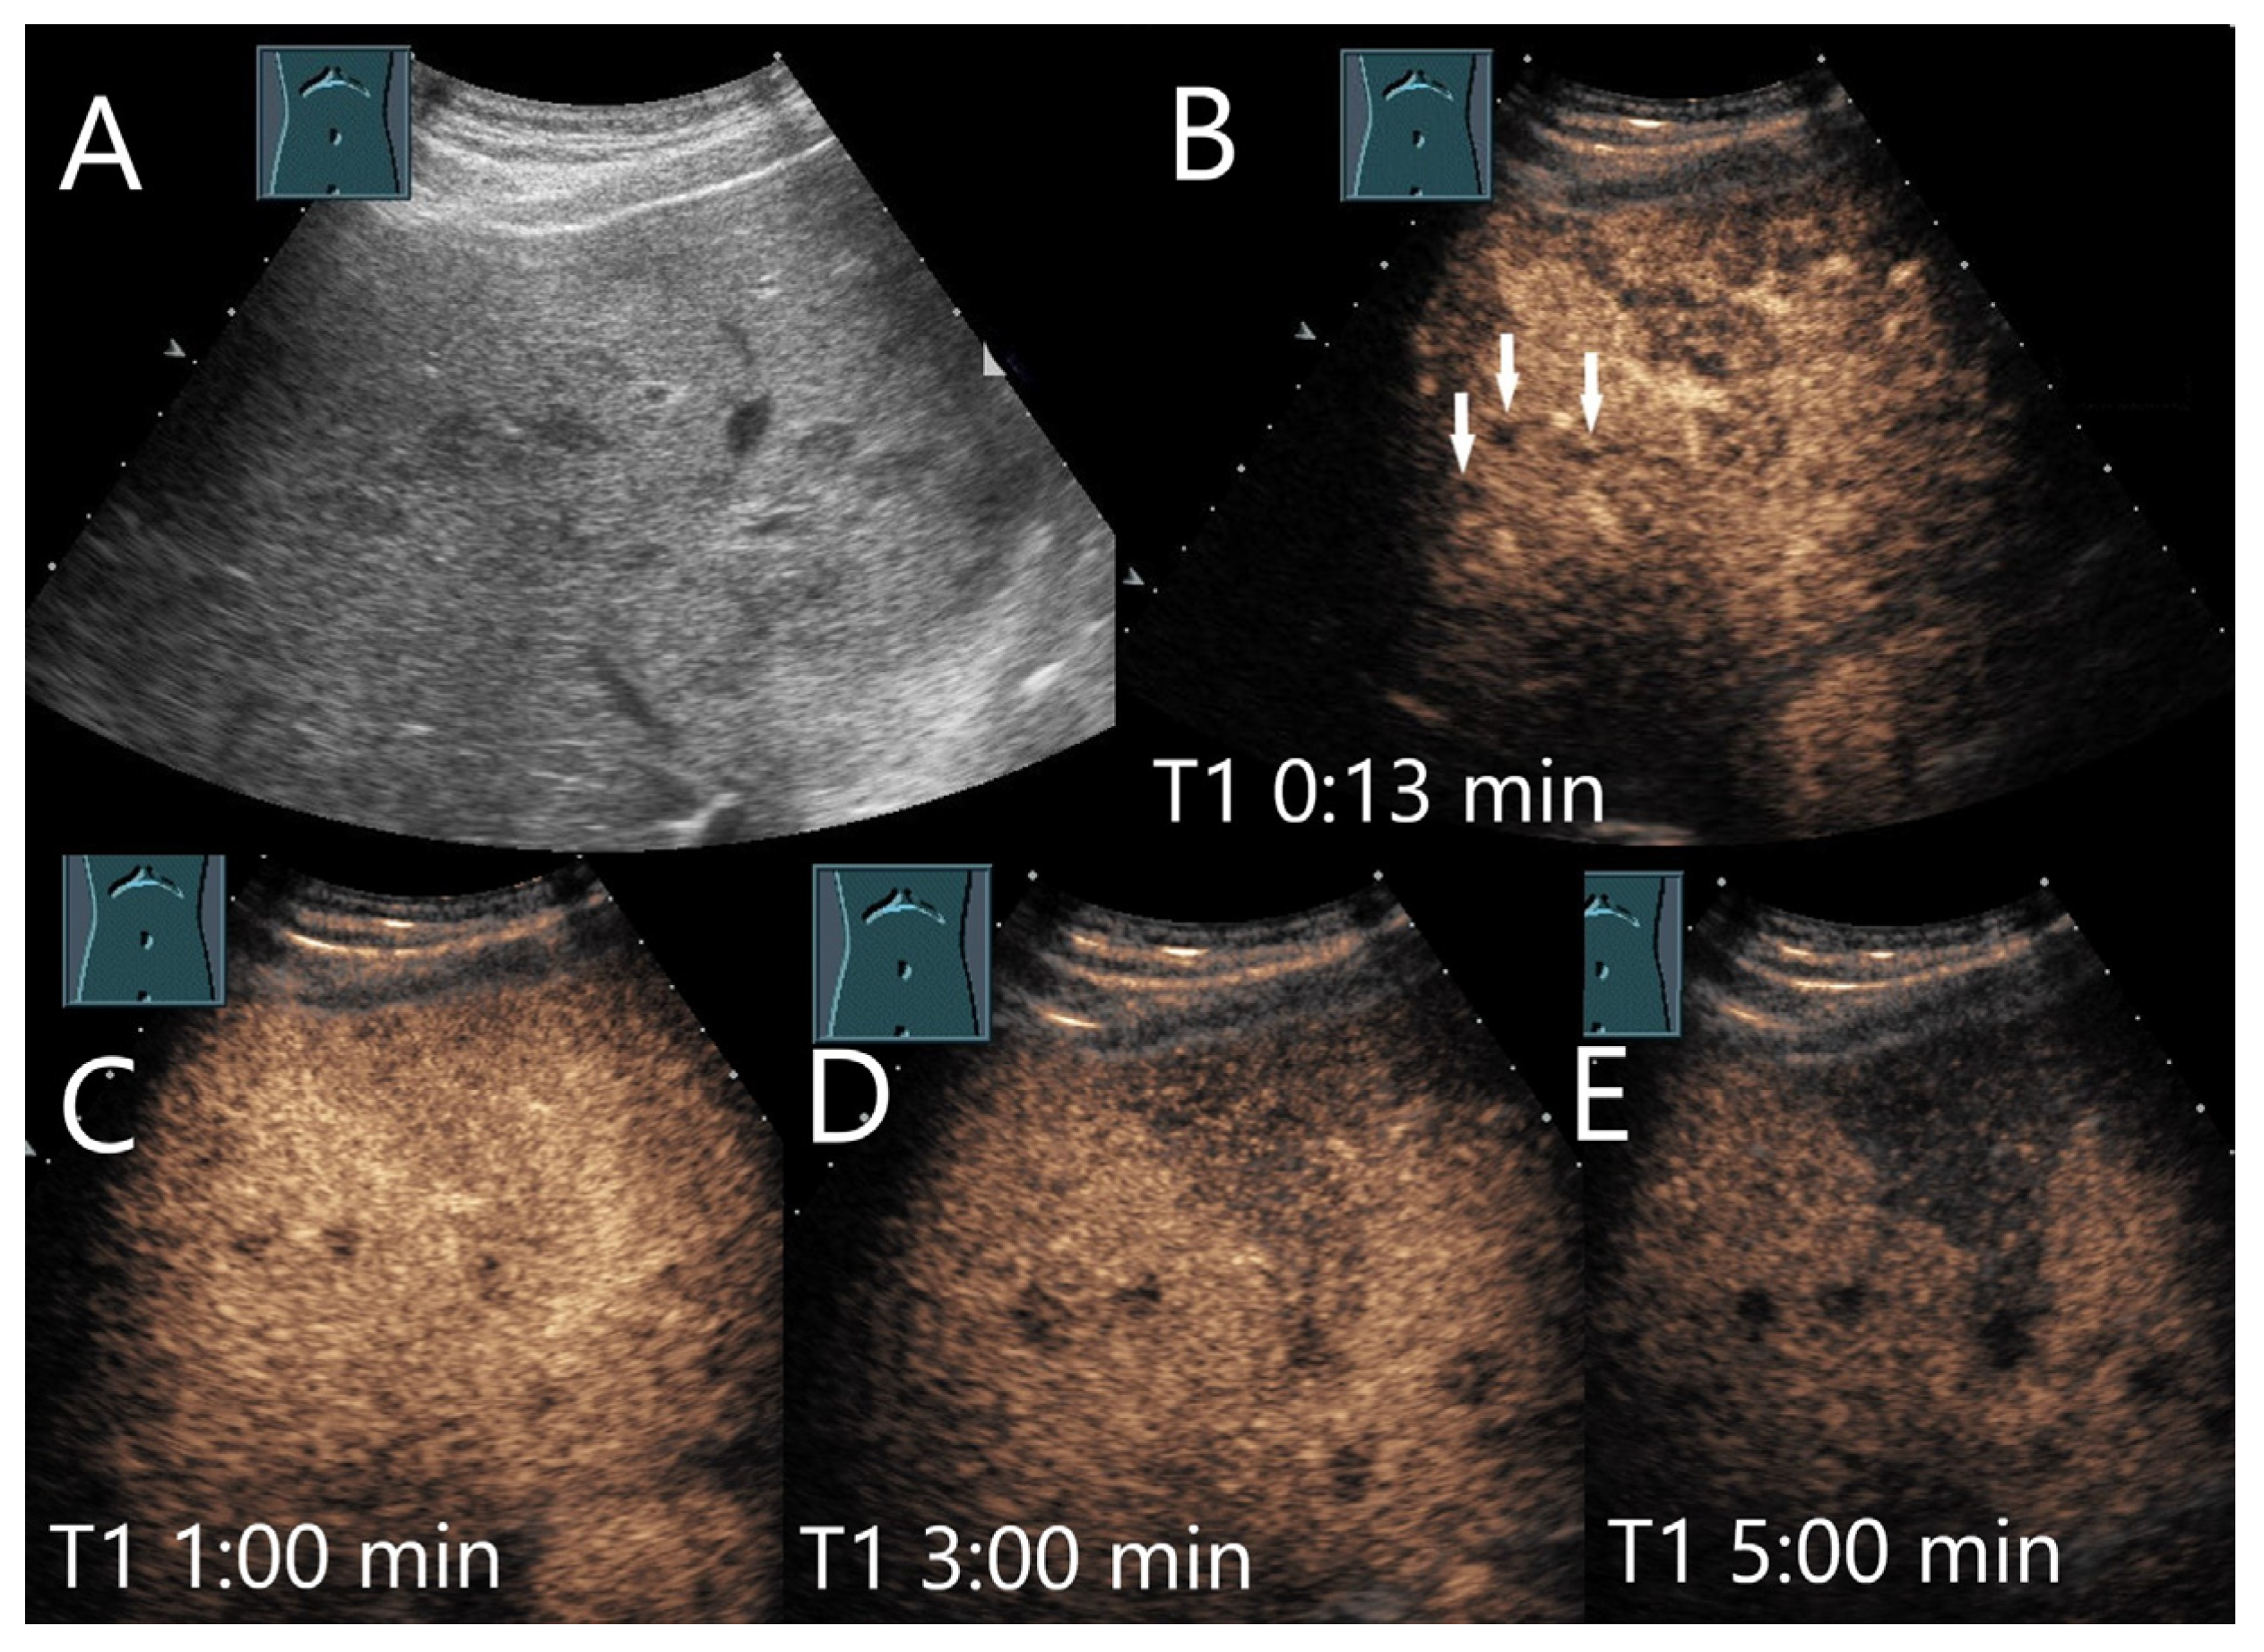

Figure 22.

Extramedullary hematopoiesis. Male patient with myelodysplastic syndrome and secondary acute myeloid leukemia and multiple hypoechoic lesions (arrows) (A). CEUS shows inhomogeneous arterial liver enhancement after 13 s (B) with slight hypoenhancement after 1 min (C) and increasing hypoenhancement after 3 min (D) and 5 min (E). In addition, a wedge-shaped lesion with slight hypoenhancement is demarcated. US-guided biopsy revealed the diagnosis of extramedullary hematopoiesis.